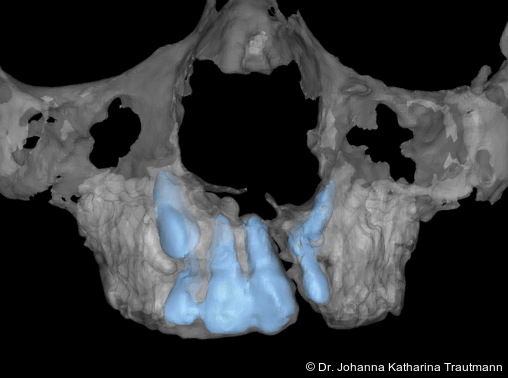

Zur genaueren Diagnostik der Lage beziehungen der Eckzähne und des Knochenangebotes im Spaltbereich kann neben den kieferorthopädi schen diagnostischen Unterlagen laut der S2 kLeitlinie Dentale digitale Volumentomografie6 auf eine dreidimensionale Bild gebung zurückgegriffen werden. In dieser zeigte sich eine vestibuläre Verlagerung des 13, eine palatinale Verlagerung des 23, sowie ein deutliches Knochendefizit im Spaltbereich mesial des hypoplastischen 22 (Abb. 2). Nach Auswertung der 3D-Daten erschien aufgrund der palatinalen Lage des 23 eine invasive Operation wie eine sekundäre Osteoplastik keinen entscheidenden Vorteil für die weitere Be handlung zu haben. In Rücksprache mit der Mund-Kiefer-Gesichtschirurgie der UMG wurde daher auf die OP verzichtet und initial die kieferorthopädische Therapie in den Vordergrund gestellt.